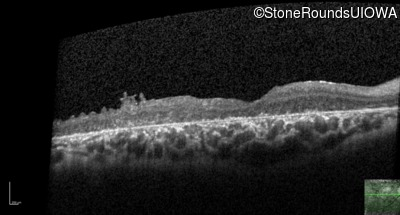

Optical Coherence Tomography - Left - 20/250 sc

Exemplar / OCT Stack